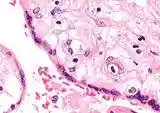

![]()

Numerous pathologies can affect the placenta.

Micrograph of CMV placentitis.